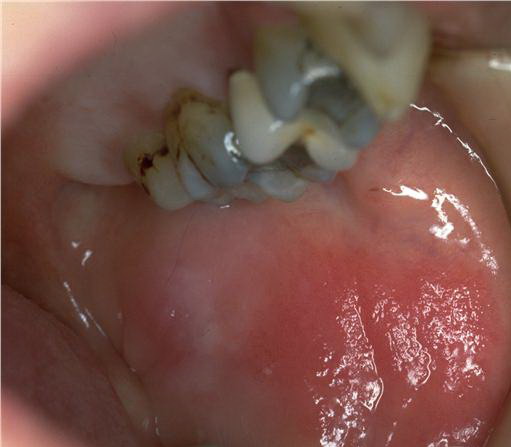

AE presents soon after weaning in affected infants or during the fourth to tenth week of life in infants who are not breast-fed. The classic features of AE include alopecia, diarrhea, lethargy, and an acute eczematous and erosive dermatitis favoring acral areas—perioral, periocular, anogenital, hands, and feet . The cutaneous findings are highly characteristic and often present initially as a non-specific, acrally distributed, symmetric, eczematous dermatitis. Over time, bullae and erosions with a characteristic peripheral crusted border develop. Patients also appear to be predisposed to systemic infections as a result of impaired cell-mediated immunity, and superinfection with Candida albicans and bacteria, usually Staphylococcus aureus, is common. Delayed wound healing, acute paronychia, conjunctivitis, blepharitis, and photophobia may also be observed. Diarrhea may be prominent but is not seen in all cases. If untreated, the disease is fatal. Acute zinc deficiency secondary to impaired absorption of zinc, inadequate intake, or excessive renal or intestinal losses may result in a clinical picture that resembles AE and occurs also in adults .